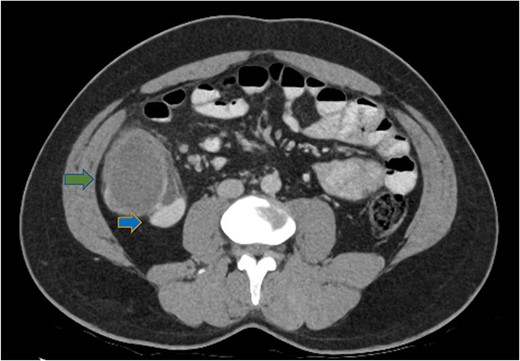

His white cell count was 12.7 × 109/L (reference range 3.7–9.5 × 109/L) and c-reactive protein was 39 mg/L (reference range ≤ 4 mg/L). Hydatid and entamoeba serologies were negative. Carcinoembryonic antigen was elevated to 11.4 ug/L (reference range ≤ 3 ug/L). Abdominal ultrasound showed an uncharacterizable RLQ cystic structure with calcification (Fig. 1). Subsequent computed tomography (CT) scan demonstrated a 56 mm × 43 mm × 58 mm ovoid ascending colon mass with central low density and rim enhancement (Fig. 2). Ileocolic lymphadenopathy up to 7.5 mm in diameter was noted with no evidence of distant metastatic disease.

Axial CT abdomen demonstrating a cystic submucosal lesion at the right colon (green arrow). There is involvement of the colonic lumen but no obstruction with oral contrasting passing through the lumen (blue arrow).